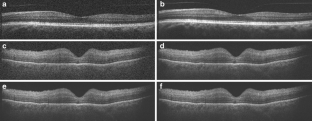

AMD pathology was detected and localized in four eyes by SDOCT. The SDOCT images correlated with the histopathology observed by light microscopy in each sectioned eye. Pathologies included a subfoveal neovascular lesion with subretinal fluid, peripapillary neovascularization, epiretinal membrane, foveal cyst, choroidal folds, and drusen. Similar imaging was possible with the simplified setup.

Fig. 1